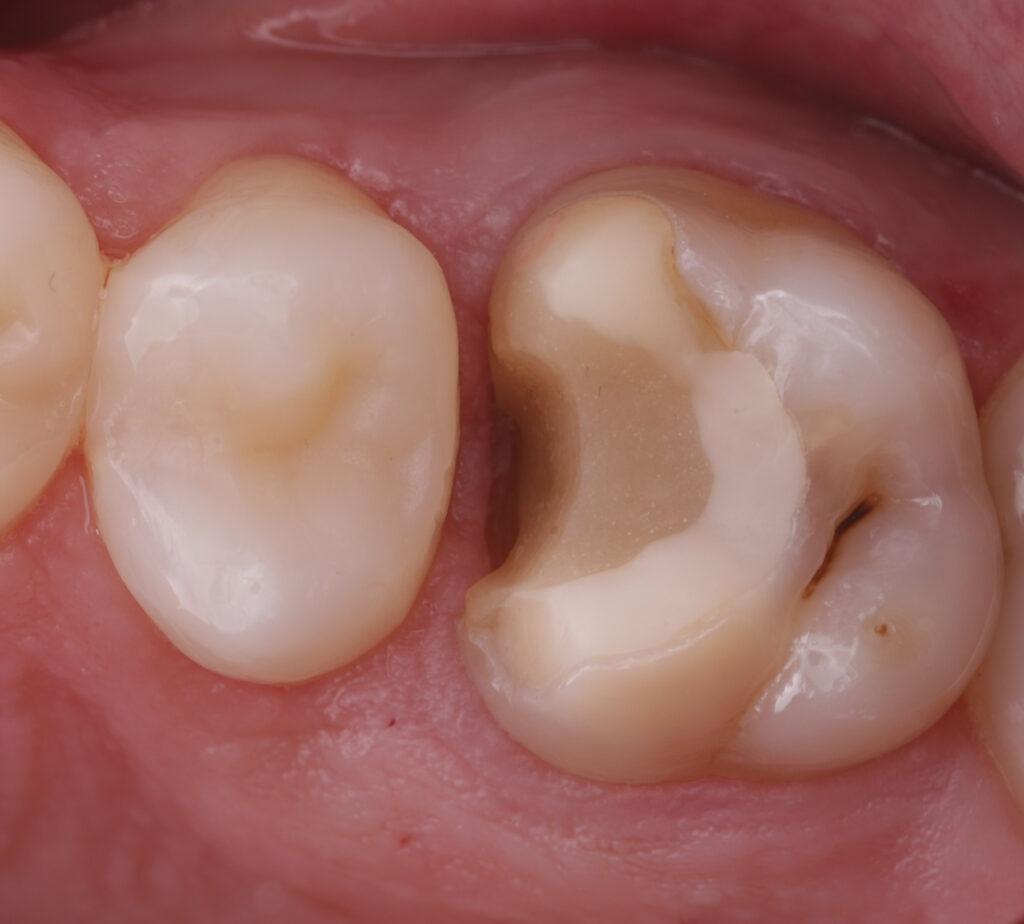

During the first visit, all carious tissues were removed, and the missing wall was restored using Asteria A3B material. The root canals were de-obturated, and a missed MB2 canal was identified. The canals were temporarily obturated with calcium hydroxide.